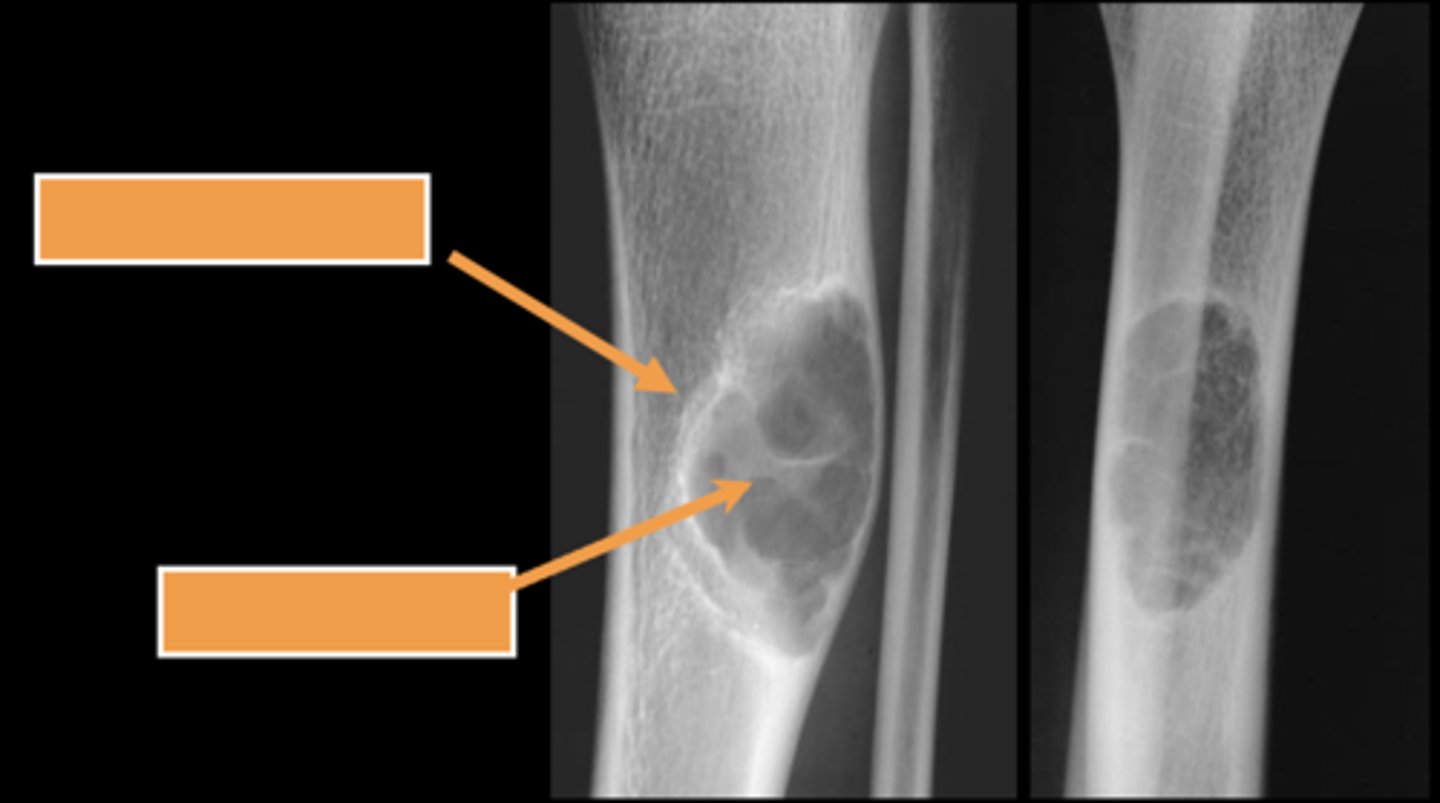

Pathologic fracture

Non-ossifying fibroma with _____

Pathologic fracture

ID radiographic feature of simple bone cyst indicated by the top arrow

Fallen fragment sign

ID radiographic feature of simple bone cyst indicated by the bottom arrow

Fallen fragment sign (10%)

- Cortex broke off

- Pathognomonic